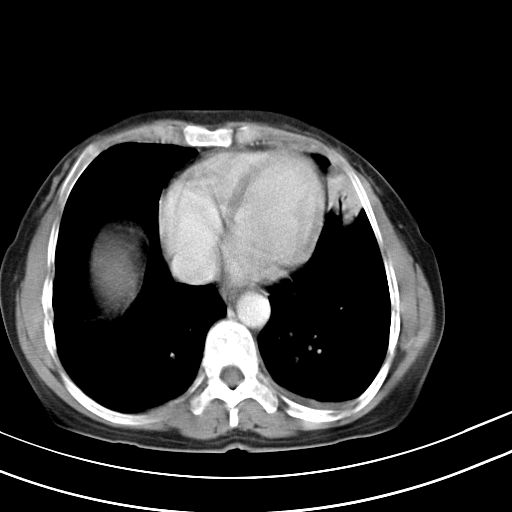

女,47岁,咳嗽胸痛一个星期,我们考虑肺结核,左下肺病灶肿瘤像不像,请高手指点。急。

考虑两肺炎症,左胸腔积液,建议治疗后复查!

考虑炎性病变,左肺舌叶病灶需要与早期肺脓肿鉴别(结合实验室),左侧少量胸腔积液。

考虑两肺炎症,建议治疗后复查,左侧少量胸腔积液

1)右肺上叶前段及左肺上叶舌段感染性病变;建议抗炎治疗后复查。2)左侧少量胸腔积液。